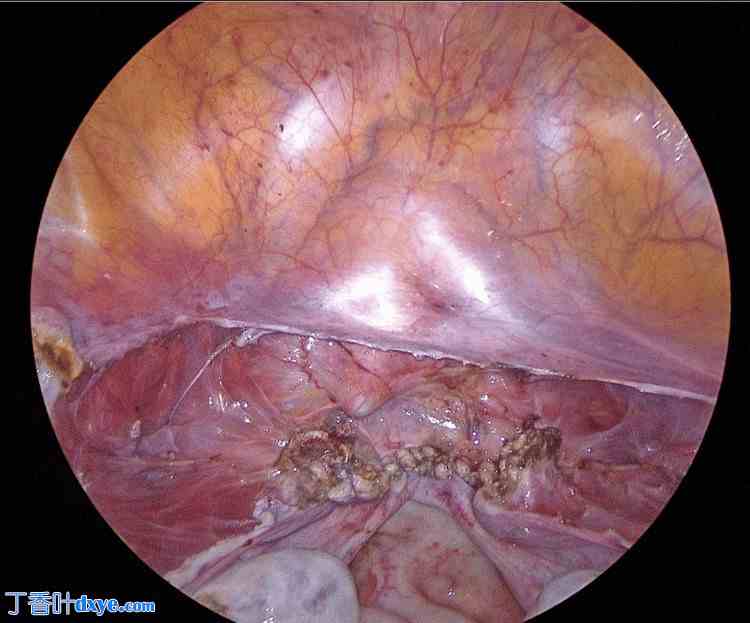

术中采用超声凝固装置,通过阴道内导管提起阴道前穹窿及后穹窿,切开阴道残端。阴道残端采用2-0多股合成可吸收缝线进行两层连续缝合(仅缝合阴道壁,不包括腹膜)(图1)。

图1. 阴道残端(首次手术)。